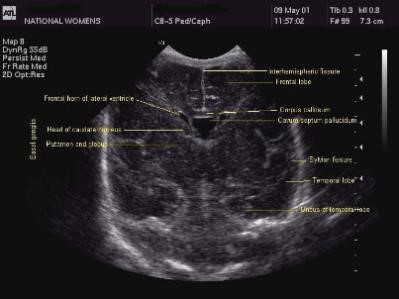

2. Anterior Horns of the Lateral Ventricles

The neonatal head ultrasound is taken by angling transducer back. You can see the CSF in the lateral ventricles as a dark image. The lateral ventricles are usually smaller in term infants than in preterm infants; however, it is common to see some variation in the size of the lateral ventricles, which is completely normal in most cases. It is also possible to see the cavum septum pallucidum that's right between the lateral ventricles. It will be larger in preterm infants.